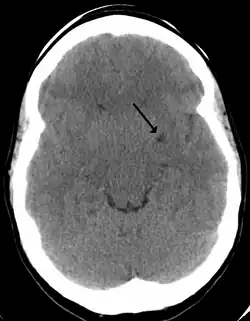

CT image showing extensive low attenuation in the right hemispheric white matter due to dilated Type 2 perivascular spaces